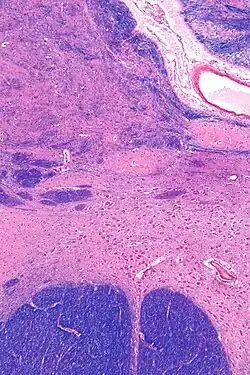

Intermediate magnification micrograph of the nucleus basalis. LFB-HE stain.